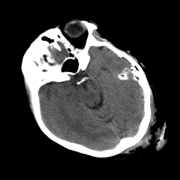

So far we have observed enhanced performance through the SA term. In this subsection, we visually illustrate how this novel term imposes smoothness between attention scores of consecutive slices, leading to more accurate predictions. Figure 2 shows plots of the attention scores assigned by SA-DMIL- and Att-MIL to the slices of three different scans (Fig. S1 in the appendix contains an analogous plot for SA-DMIL-). As expected, introducing the SA loss results in smoother attention weights. Note that the smoothness constraint of SA-DMIL effectively penalizes the appearance of isolated non-smooth attention weights that incorrectly jump over or below the threshold.

We also include visual examples of consecutive CT slices in Fig. 3. In Scan 1, the baseline Att-MIL produces a wrong prediction at scan level. When using SA, the prediction is correct since dependencies between adjacent slices have been learned. In Scan 2, both models produce correct predictions at scan level, but SA-DMIL is more accurate at slice level. This occurs thanks to the SA loss, that turns the attention scores into smoother values and, therefore, avoids random jumps up and down the decision threshold.